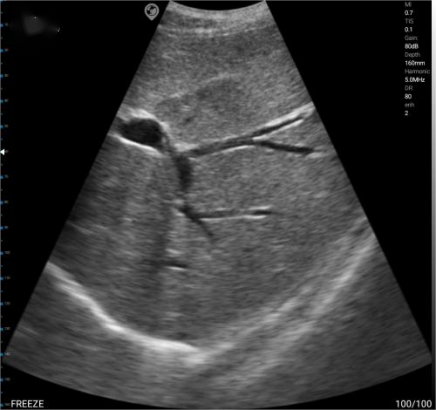

Ultrasound imaging utilizes the probe to emit ultrasonic waves, which scan the human body. Due to the varying acoustic impedance of tissues, reflected ultrasonic waves are generated. The probe receives the reflected ultrasonic waves and converts them into electrical signals, which are then processed by the system to display as different images.

In sonograms, various echo imaging patterns are primarily caused by differences in acoustic impedance. As shown in the figure above, due to the high acoustic impedance of bones, they appear as high echoes on the image. The general order of acoustic impedance values is: Air <Fat <Water <Blood <Kidney <Liver <Muscle <Skin <Bone